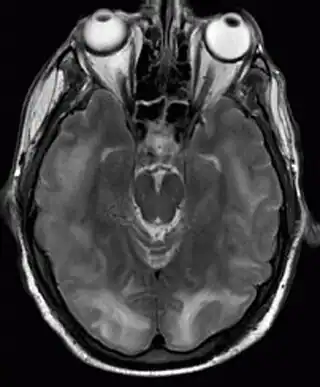

![]() Resonancia magnética nuclear en la que son visibles lesiones de encefalopatía posterior reversible. | ||

El síndrome de encefalopatía posterior reversible, también llamado síndrome de leucoencefalopatía posterior reversible (RPLS por sus siglas en inglés), es un trastorno neurológico de inicio brusco que se presenta con dolor de cabeza, disminución del nivel de conciencia, convulsiones, trastornos visuales y déficits neurológicos focales.[1] En las imágenes obtenidas mediante resonancia magnética nuclear de la cabeza, se visualizan áreas de edema cerebral en la sustancia blanca que afecta predominante a las regiones posteriores del cerebro, principalmente al lóbulo parietal y al lóbulo occipital. El pronóstico a largo plazo es bueno, produciéndose por lo general recuperación completa, aunque en ocasiones persisten secuelas irreversibles. La mortalidad es de alrededor del 6%. El cuadro se asocia a diferentes circunstancias, algunas de las más frecuentes son: tratamiento con medicamentos inmunosupresores o quimioterápicos, hipertensión arterial, infecciones graves o sepsis, enfermedades autoinmunes como el lupus eritematoso sistémico y la púrpura trombocitopénica idiopática, insuficiencia renal y preeclampsia. La causa y el mecanismo fisiopatológico que provocan el síndrome no se conocen con exactitud, podría deberse a lesión en el endotelio de los vasos sanguíneos cerebrales por cambios bruscos en la presión arterial, o a la acción de sustancias llamadas citocinas que dañarían el endotelio de la pared de los vasos. [2][3]